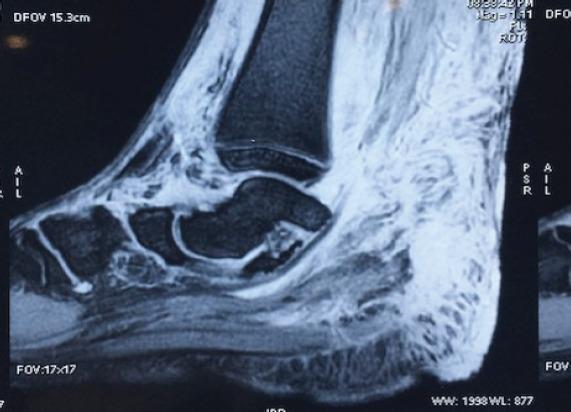

A 16-year-old male presented with painless swelling on the posteromedial aspect of the lower right tibia, which was confirmed to be a dysplastic mass on biopsy. Physical examination also revealed cafe au lait macules and axillary freckling, leading to a diagnosis of NF-1.

Bony lesions in NF-1 patients mainly include the spine and tibia. Congenital tibial dysplasia is commonly associated with NF-1 and may progress to pseudoarthrosis if early management is not started. Treatment modalities include excision, bracing, and fixation.